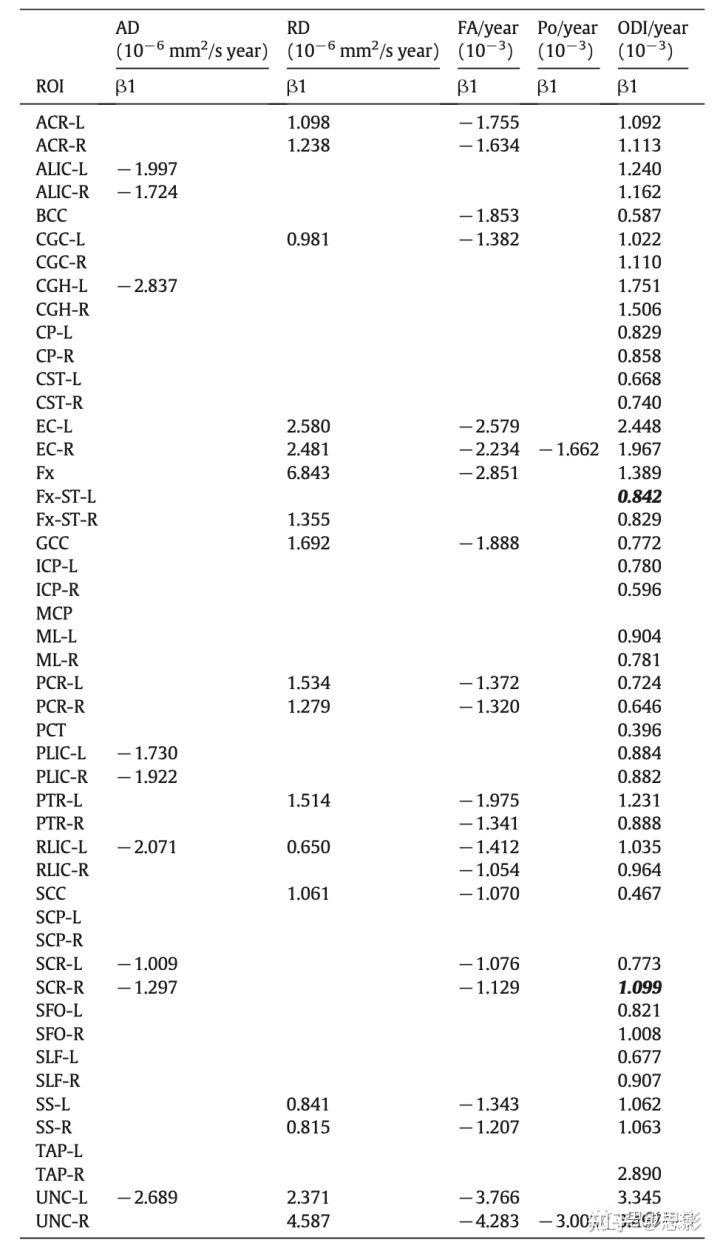

因为在回归模型1中,所有的扩散指标和ROI组合下β3都不显著,因此老化效应在两性中是一致的。因此,无论是回归模型2还是回归模型3的β1都被用来描述男女共同的老化效应。表3总结了白质ROI中那些显著的β1(斜率),图4显示了这些斜率每十年的变化百分比。图5为年龄相关的重要ROI中DTI和q空间分析的显著回归曲线。ODI的回归线如图6。DTI扩散指标随年龄变化的总体趋势是AD降低,RD增加,FA降低。MD在年龄上没有显著差异。同样,组织限制(P0)在大多数白质ROI中相对稳定,但在2个ROI中(包括钩状束,UNC)显著下降。与年龄相关的NODDI指标变化的总趋势是增加了纤维弥散度(ODI),其中显著的白质ROI发生率最高。轴突内体积分数(ICVF)稳定,所有白质ROI无显著变化。

表3 结果表明:男性和女性扩散指数的共同老化速率β1显著。当模型2的β2显著时,将模型2(Eq.8)的显著β1列出来(粗体斜体)。当模型2的β2显著(意味着回归模型2退化为模型3)时,将模型3的显著β1列出了(Eq.9)。白质ROI的全名见表1,解剖位置如图2所示。

扩散指标之间的关系

如表3和表S2所示,19%的FA-显著降低的ROI的AD也显著降低,76%的FA-显著升高的ROI的RD显著升高,AD降低或RD升高的情况下FA-显著变化的ROI为86%,所有FA-显著ROI的ODI均升高。所有AD和RD显著变化的ROI也随着年龄的增长而发生显著的ODI变化,只有一个RD显著的ROI。FA、AD和RD与ICVF或P0无关。

扩散指标中与年龄相关的定量变化

图4显示了各ROI的扩散指标的百分比变化。AD每10年下降1%-3%。在大多数ROI中,RD每10年增长3%-7.0%,但在右侧钩状束中,RD激增至12%。FA每十年下降1%-8%。P0下降了3%和8%。ODI增长了3%-16%。年龄相关的关键ROIs包括钩状束、穹窿和海马扣带回段,其变化率往往高于其他白质ROIs。

对年龄敏感的白质ROIs

在所研究的48个白质ROIs中,双侧外囊、内囊的后侧部分和钩状束对衰老最敏感,4个弥散指标具有显著的年龄相关变化(表3和图4)。年龄相关的关键ROI包括左侧扣带和穹窿,3种不同弥散指标的变化对衰老具有高敏感性,而其他年龄相关的关键ROIs,包括双侧海马带段和终末横纹穹窿的敏感性为中低。双侧前/上/后放射状冠层和矢状层对衰老中度敏感。这些白质ROI与涉及高级认知功能的大脑皮层相连。连接左右脑、胼胝体膝部和压部的白质纤维对衰老也很敏感。